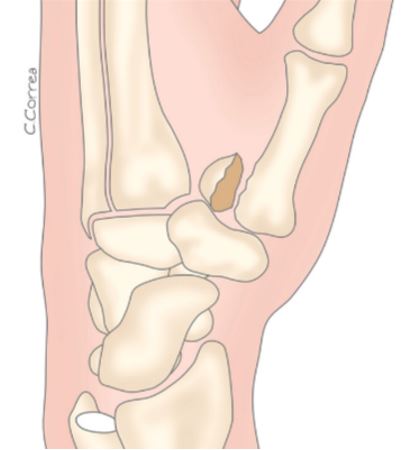

Lesión de Benet: es una fractura característica que afecta la base del primer metacarpiano, justo donde se articula con el hueso trapecio en la base del pulgar. En ciclistas, suele producirse por una caída en la que el pulgar impacta contra el manillar, transmitiendo la fuerza hacia la base del dedo. Este tipo de fractura, aunque pequeña, compromete la estabilidad de la articulación y puede generar dolor intenso, inflamación y pérdida de movilidad si no se trata adecuadamente. Es fundamental reconocerla pronto y buscar atención médica, ya que a menudo requiere reducción y, en algunos casos, tratamiento quirúrgico para evitar secuelas funcionales.